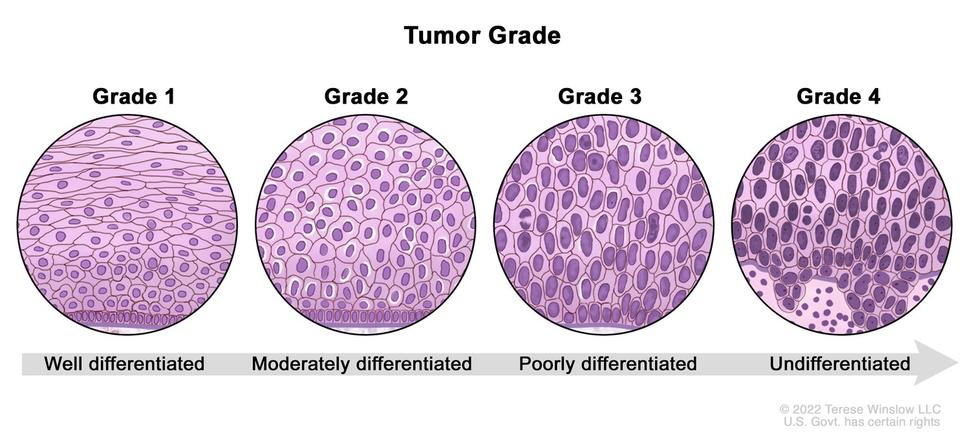

What Is A Clear Margin In Breast Conserving Cancer Surgery? | SpringerLink

link.springer.com

margin conserving surgery breast cancer clear figure